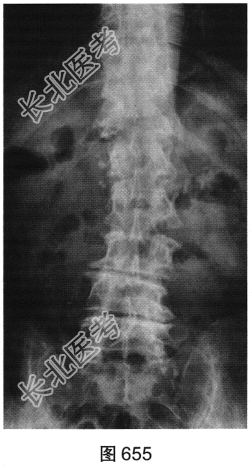

- 多项选择题2.[提示]患者行腰椎X线及CT检查,见图655~图659。患者有哪些阳性影像学表现( )

A、椎间盘“真空现象”

B、腰椎前滑脱

C、椎间盘膨出、突出

D、腰椎轻度侧弯

E、椎小关节骨质增生硬化

F、腰椎间隙变窄